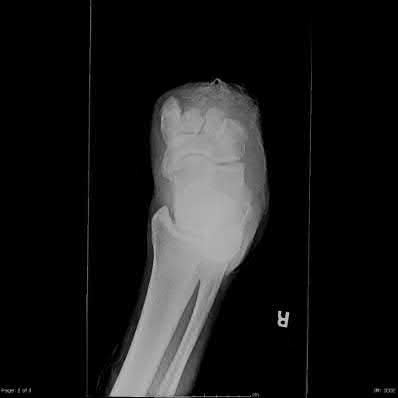

Question 9:

A Schatzker Type IV fracture involves a fracture of the medial tibial plateau. Unlike lateral plateau fractures (which are typically low-energy valgus injuries), a medial plateau fracture usually results from a high-energy varus force combined with an axial load. This mechanism places extreme tension on the lateral-sided structures, frequently leading to associated Lateral Collateral Ligament (LCL), posterolateral corner, and/or peroneal nerve injuries.